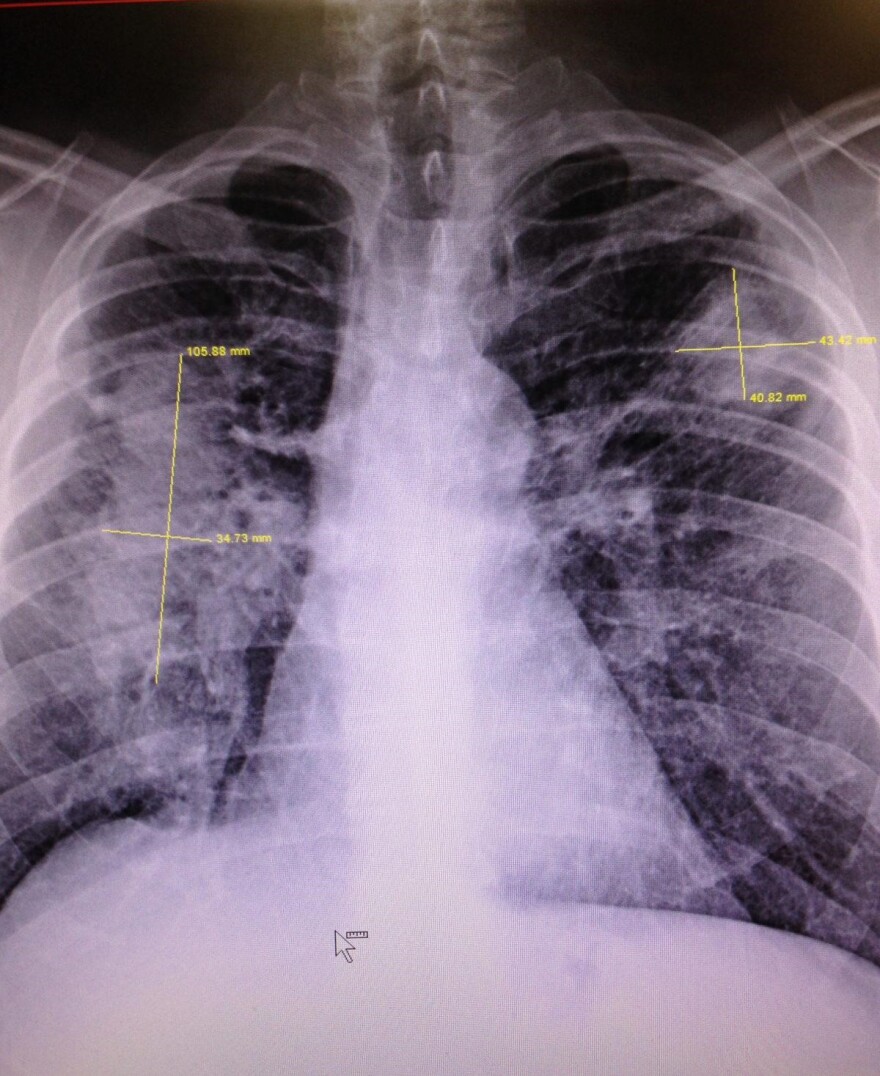

An X-ray image of an Appalachian coal miner with black lung lesions.

Doctors hired by coal companies in black lung cases are far less likely to diagnose the disease in X-rays than are independent doctors or those who are hired by coal miners, a new study has concluded, pointing to conflicts of interest in the system that sick miners use to receive assistance.

The doctors who worked for coal companies to read the chest X-rays of miners found an absence of the disease nearly 85% of the time, according to the authors of the study, published Friday by the University of Illinois Chicago School of Public Health’s Division of Environmental and Occupational Health Sciences. In contrast, the doctors whose clients were coal miners found an absence of black lung a little more than 51% of the time.